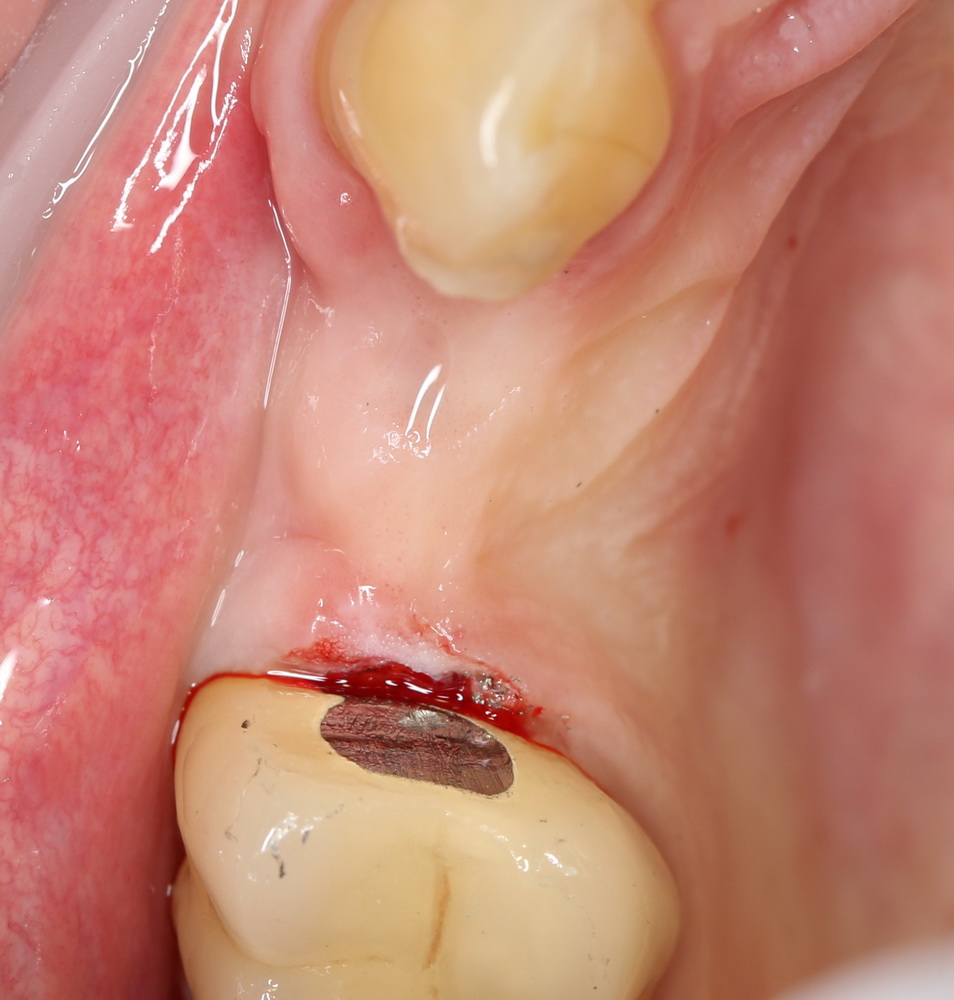

параллельно восстанавливая достаточный слой прикрепленной десны. Через неделю:

Осталось еще немного подождать, контурировать десну и отправить пациентку на временное протезирование. До профосмотра после протезирования пациентка еще не дошла, поэтому результаты протезирования я покажу Вам позже. Но точно знаю, что результатом она довольна.